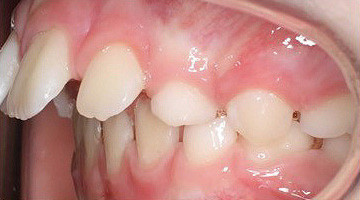

Klinisches Fallbeispiel 1 (Abb. 1a–u)

Neunjähriger Patient mit deutlich vergrößertem Overjet aufgrund eines Distalbisses in Kombination mit einer Protrusion der Oberkieferfront. Habits bzw. myofunktionelle Aspekte wurden adressiert. Die Behandlung erfolgte mit einem Invisalign-Schienensatz (56 Aligner) mit Precsion Wings im Rahmen einer Frühbehandlung zur Prophylaxe eines Frontzahntraumas.